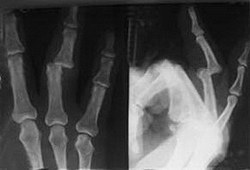

Вывихи костей кисти составляют 5% от общего числа вывихов. Причиной травмы обычно становится падение с упором на кисть или прямой удар в область лучезапястного сустава. Особенности вывиха кисти определяются анатомическим строением сустава, положением кисти и направлением действия сил, вызывающих травму. Вывихи костей кисти классифицируют на истинные, перилунарные, периладьевидно-лунарные, перитрехгранно-лунарные, чрезладьевидно-перилунарные, чрезладьевидно-чрезполулунные, вывихи пястных костей и фаланг пальцев. Клиника вывиха кисти складывается из отечности и боли в области вывиха, при осмотре выявляется наличие деформации. Диагноз подтверждается с помощью рентгенографии.

В образовании лучезапястного сустава участвуют сверху - суставные поверхности лучевой и локтевой костей, снизу - восемь мелких костей запястья. Кости запястья расположены в два ряда. Определенные анатомические особенности лучезапястного сустава обуславливают вывихи полулунной и ладьевидной костей, расположенных в верхнем ряду запястья. Остальные кости запястья вывихиваются редко.